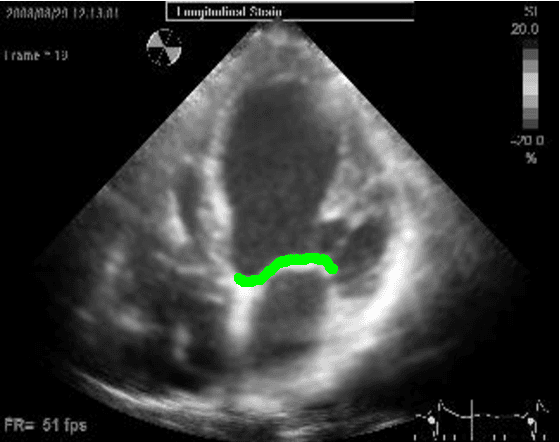

Abstract:Left ventricular segmentation is essential for measuring left ventricular function indices. Segmentation of one or several images requires an initial guess of the contour. It is hypothesized here that creating an initial guess by first detecting anatomical markers, would lead to correct detection of the endocardium. The first step of the algorithm presented here includes automatic detection of the mitral valve. Next, the apex is detected in the same frame. The valve is then tracked throughout the cardiac cycle. Contours passing from the apex to each valve corner are then found using a dynamic programming algorithm. The resulting contour is used as an input to an active contour algorithm. The algorithm was tested on 21 long axis ultrasound clips and showed good agreement with manually traced contours. Thus, this study demonstrates that detection of anatomic markers leads to a reliable initial guess of the left ventricle border.